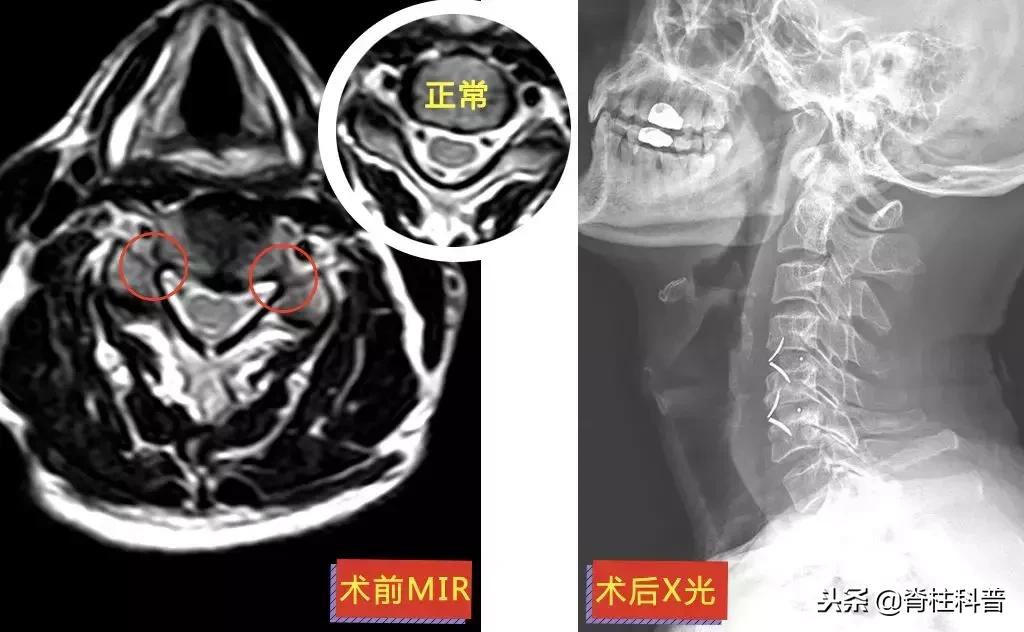

廖四爷(化名)4年前第一次发病:右上肢刮骨样疼痛和乏力。而后的每一次发病,他都只接受牵引等保守治疗,长达4年。可保守治疗的效果逐渐减退。2018年8月23日前来就诊时,廖四爷的右上肢上臂已经出现肌肉萎缩。

▲ 廖四爷:术前MRI与术后X光

11月26日,在张主任的门诊,廖四爷回来复诊。情况还不错,上肢刀割样的疼痛已经消失,照了CT内固定也长得很好,但是萎缩的手臂还没得到恢复,还需要接受康复治疗。